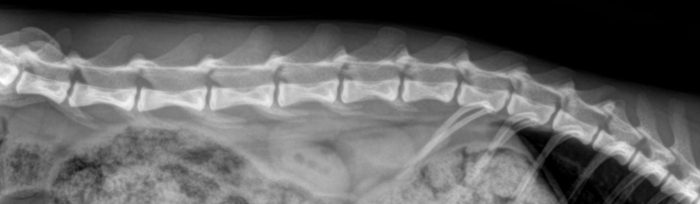

In de onderstaande foto’s is het verschilt te zien tussen een ruggenwervel van een kat zonder en met artrose. Hierbij is de artrose aangegeven met rode pijlen. Bij een röntgenfoto beoordeeld de arts of er aanwezigheid is van een versmalling van de gewrichtsspleet, wat duidt op een afname van het kraakbeen.